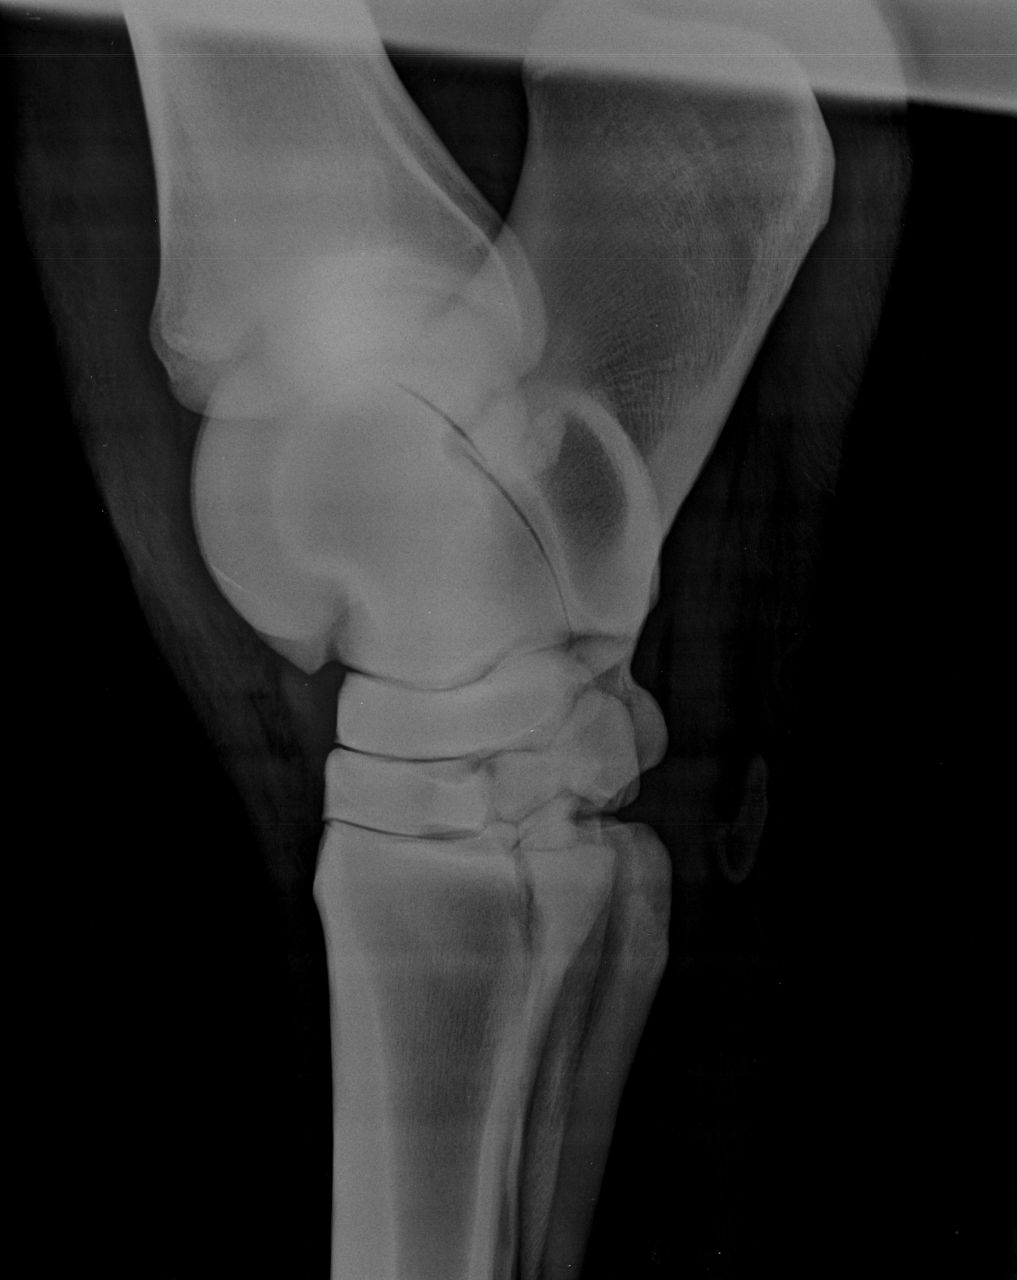

| Dire merci | donc, voilà ... ensuite, il recommence à travailler bien, on essaie quelques barres à nouveau et ça va pas mal du tout ... toujours pareil : franc, allant ... Mais je l'emmène chez le véto, je veux mon contrôle ... BIlan (je ne l'ai pas j'ai juste les radios) : sur le cercle bon à droite c'est pas top. On été fait aussi au passage une echo du grasset pour être certain qu'il n'y ai pas de soucis plus haut. Une anesthésie de je ne sais plus quel nerf, après laquelle ont été refait les tests de flexion et sur le cercle. Amélioration mais très légère et pas assez franche, donc radios du jarret. cheval "gêné" aux tests mais pas boiteux, toujours pareil. c'est pas franc. EPARVIN en formation (on voit à peine l'augmentation de la densité au niveau de l'interligne) mais cette année ON VOIT ! quelque chose de concret Halleluiah ! et en plus y'a autre chose, il demande un avis chir et va montrer les radios à son collègue et dois me rappeler. ... |

| Dire merci | une carrière pas top à un manège et carrière en sable de fontainbleau...et ba..rien à voir.. (le rêve tu m'étonnes) ça c'est certain ! le sol est important. J'ai eu la chance d'avoir toujours de bons sols sauf où je suis le manège est pas terrible. Du coup on se promène pour travailler en LP. Notre piste de galop n'est pas dégueu et on va y passer du temps je pense à marcher... Je suis assez partante pour le TILDREN d'emblée. Je me posais la question en été dernier déjà mais je suis assez contre la chimie quand rien n'est déclaré. Et rien n'était déclaré .... !! c'était mon SEUL soucis. du coup j'avais arrêté de sauter jusqu'en hiver. On a repris sur petit, ça allait bien. L'irrégularité était présente quand on a recommencé après un mois d'arrêt. Mon instructeur soupçonnait surtout un manque de muscle ou une raideur de "repos". Bon moi certains mouvement, en liberté me faisaient tiquer et je "sentais" que quelque chose n'allait pas mais c'était pas CLAIR. alors une petit radio (pour peu que quelqu'un sache les lire vraiment .... ) ![]() ![]() les radios comme dit ont l'air saines ...pour les fragments osseux il y a encore 4 clichés obliques (que je n'arrive pas à charger... ) |

| Dire merci | si, les radios il faut regarder entre les os, les liserés foncés : quand ça devient "flou" et plus épais, c'est signe de remaniement |